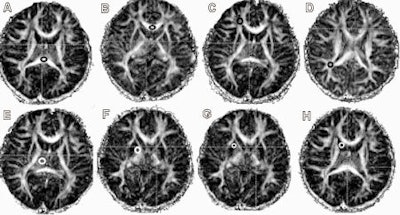

| The clinical images are representative region-of-interest placements on fractional anisotropy maps for the seven regions studied. Thalamus (E), globus pallidus (F), putamen (G), caudate (H), and white matter regions [frontal white matter (C) and parietal white matter (D)] were drawn bilaterally, while corpus callosum was drawn as indicated in the splenium (A) and genu (B). Images courtesy of Neurology and the University of Hawaii at Manoa. |